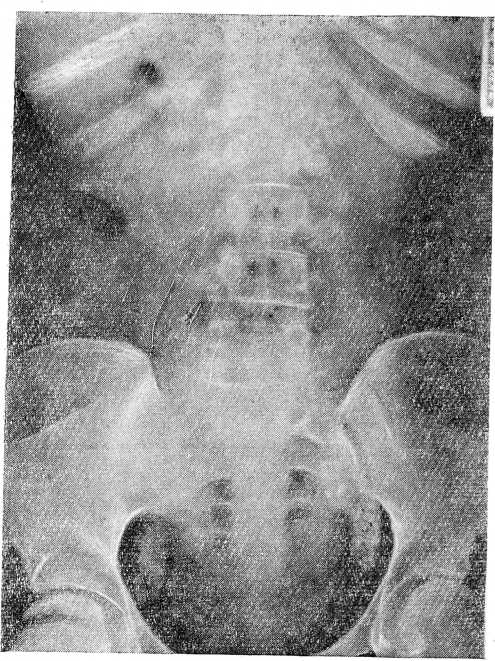

При рентгенологическом обследовании органов грудной клетки обнаружено множественное обызвествление всех групп лимфатических узлов: шейных, парабронхиаль- ных, бифуркационных, грудных, мышечных.

На рентгенограмме нижних грудных и пояснично-крестцовых позвонков наблюдалось множественное обызвествление лимфатических узлов, расположенных по краям позвоночника и в тазу (рис. 2). Через 2 месяца выявилась деструкция 11 и 12 грудных позвонков.

Рис.2